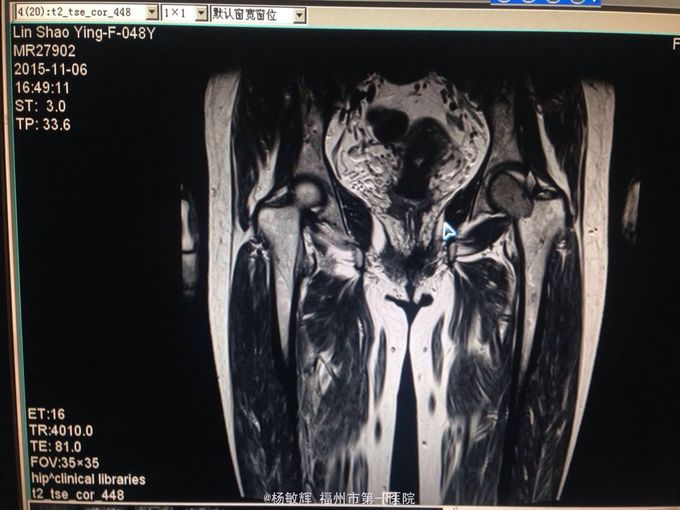

女性,48岁,以“左髋部疼痛伴活动受限2年”为主诉入院。缘于入院前2年无明显诱因出现左髋部疼痛不适,疼痛呈间歇刺痛,无向他处放射,伴左髋部活动受限,间歇性跛行,就诊当地医院查髋部X线提示:骨质破坏。MRI提示:左股骨头异常信号。当地医院诊断股骨头占位,未予以特殊处理,2周前疼痛加剧,就诊我院,查左髋部MRI提示:左髋部占位,骨巨细胞瘤可能性大。入院后于穿刺活检送病理,病理结果:左股骨头骨巨细胞瘤。拟:左股骨近段骨巨细胞瘤,收住院。

左股骨近段骨巨细胞瘤 入院后完善相关术前检查,未见明显手术禁忌症,行:左股骨近段占位切除+人工髋关节置换术